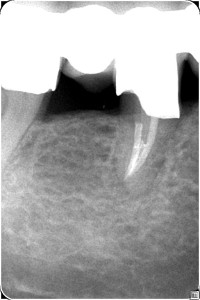

Fallbeispiel-3_Bild_5_Pat_563_Za_46_R__ntgenkontrolle_n_2_5_Jahren Posted on 5. Februar 201615. Februar 2016 by Administrator